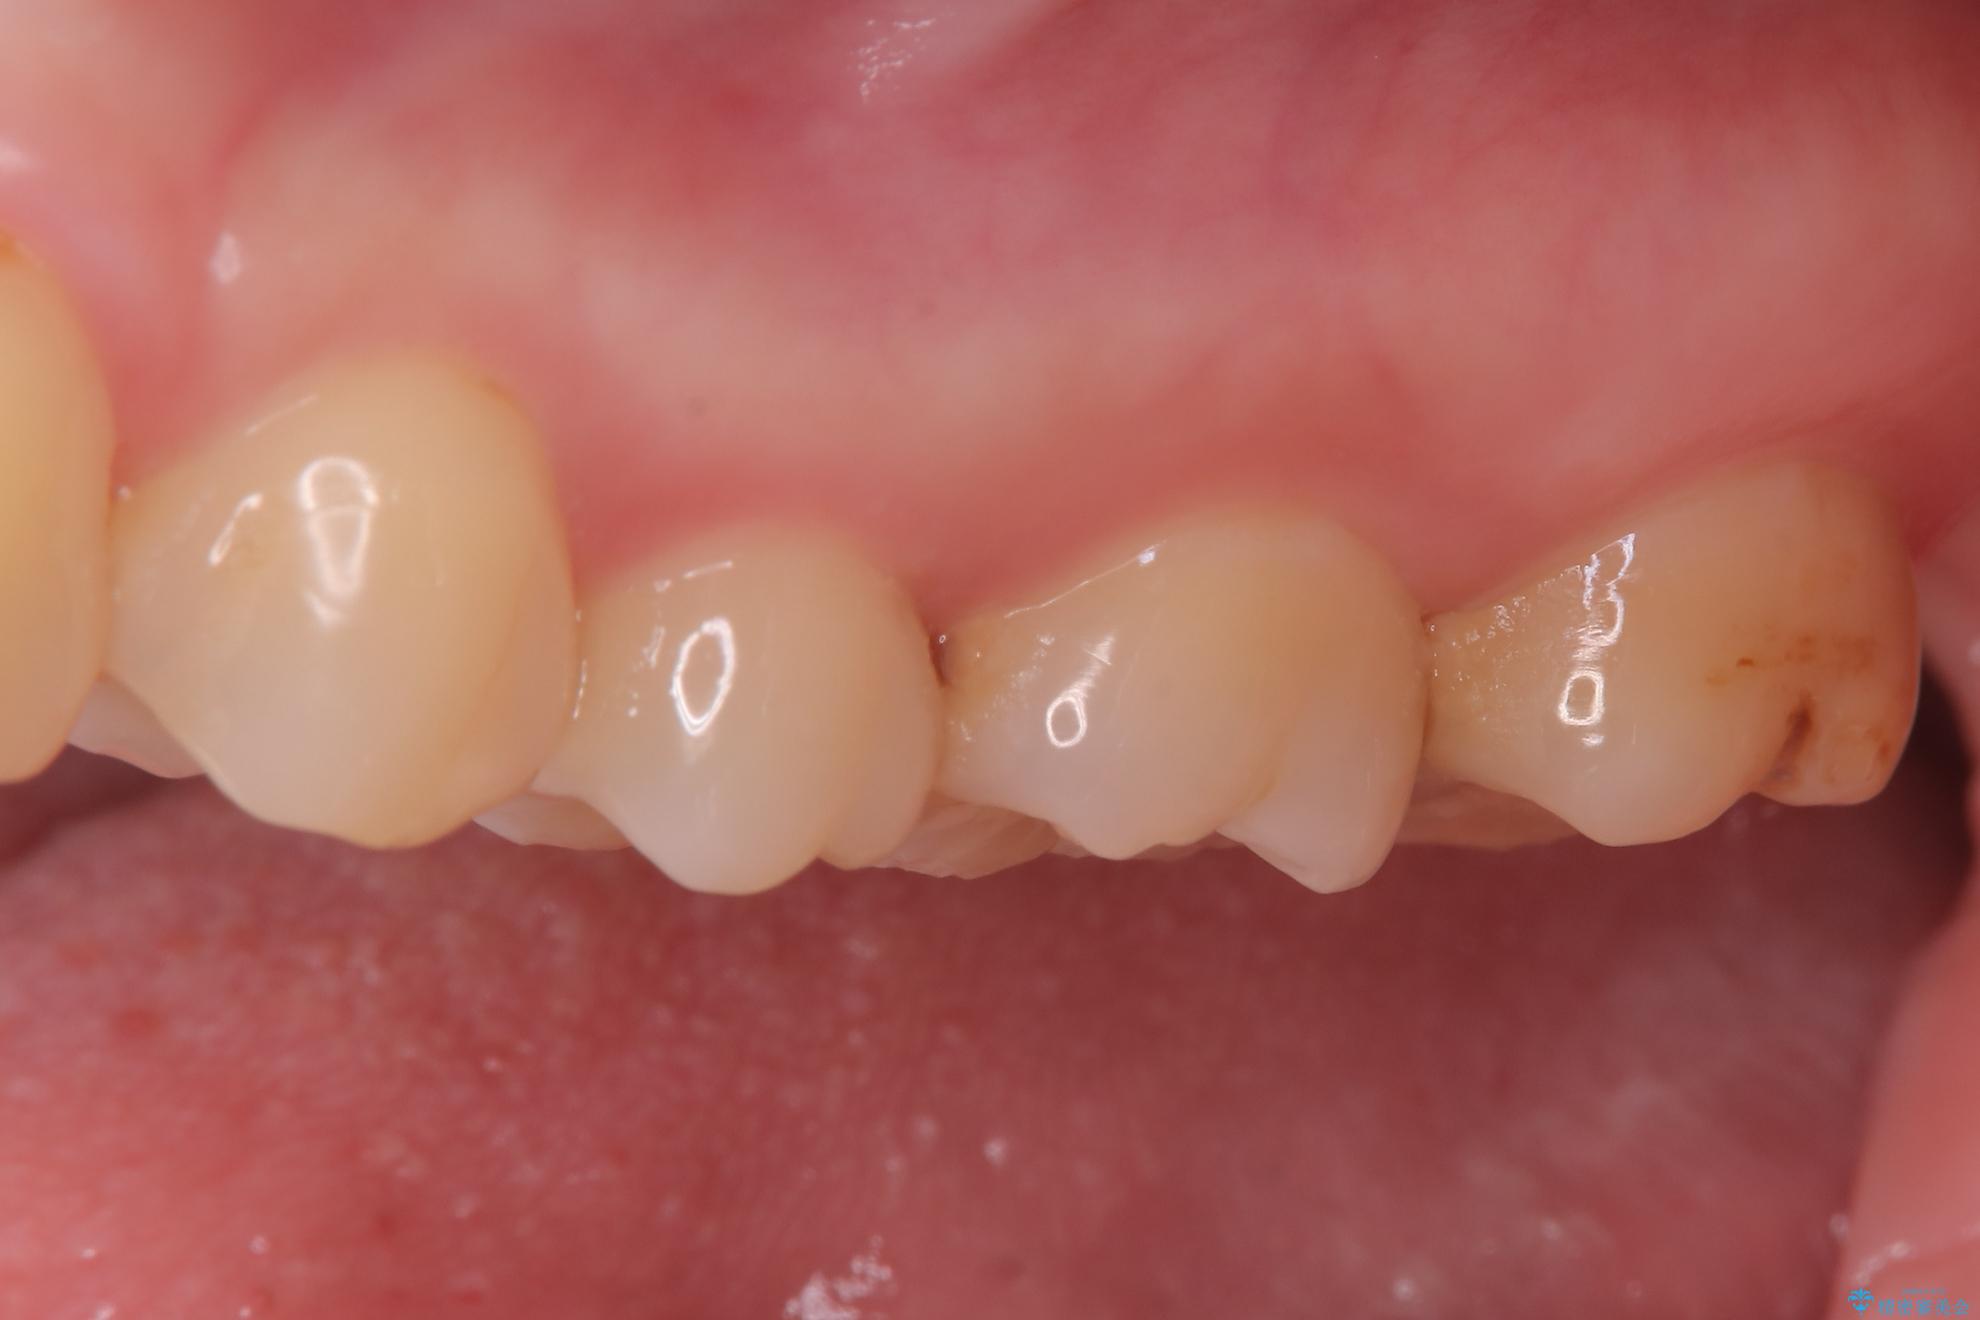

短期間での治療を可能にしつつ、天然歯と見分けがつかない審美性と、長期的に安定する機能性を兼ね備えたセラミック修復を実現しました。

比較的軽度な虫歯には、セラミックインレー(詰め物)で対応し、健全な歯質を最大限に残しました。

進行した虫歯や歯の強度が低下している歯には、セラミッククラウン(被せ物)を選択し、歯全体を保護することで破折を防ぎました。